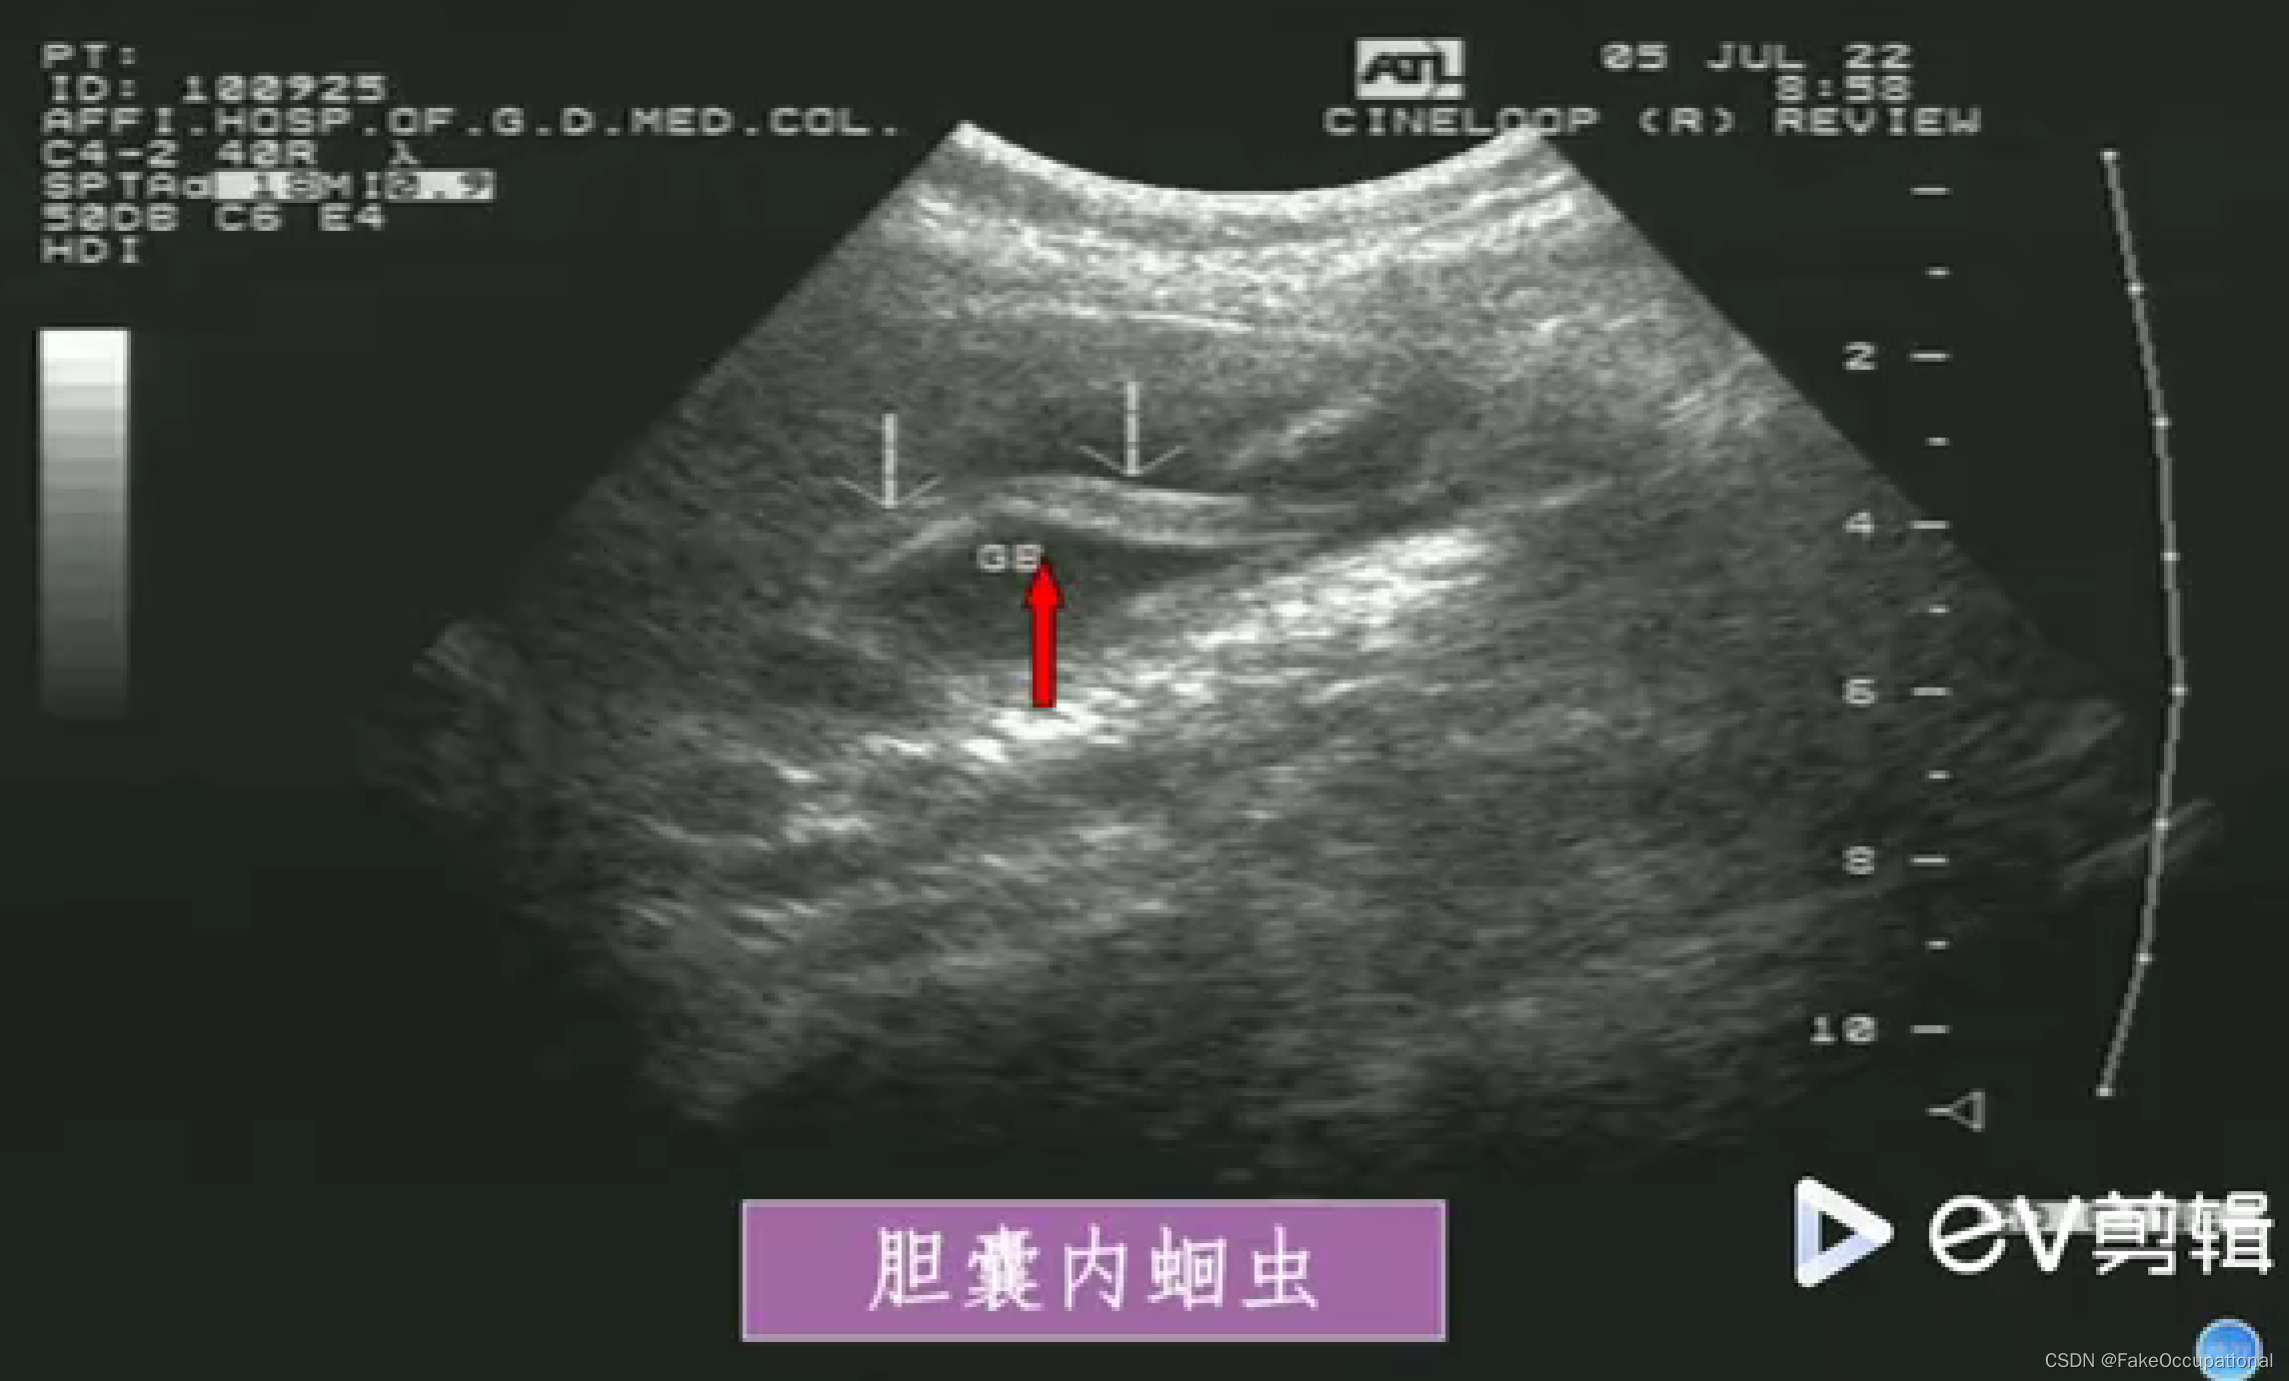

超声声像图: - 肝外胆道不同程度扩张

- 扩张胆管内可见蛔虫回纵切面为双线状长条形的平行高回声带,中央可见暗带;黄切面为“同心圆”状

- 活蛔虫可见其蠕动征象具有特异性诊断意义

- 死蛔虫:虫体萎缩,多节段性光带,中央暗带模糊或消失